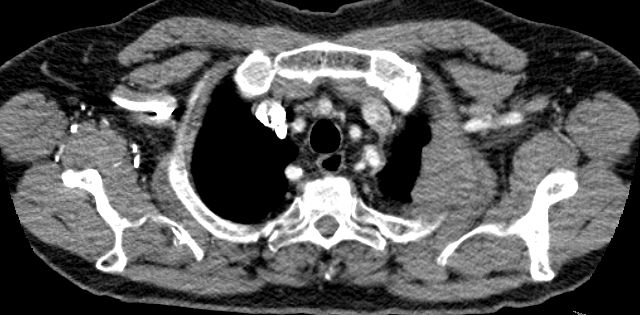

| Pancoast rechter Oberlappen | 66-jährige kachektische Frau mit Nikotin- und

Alkoholabusus, die zur Abklärung eines juckenden Exanthems der Arme und des

Halses zur Aufnahme kam. Keine Schmerzen, keine Armschwellung rechts.

Belastungsdyspnoe bei Emphysembronchitis.![]() |